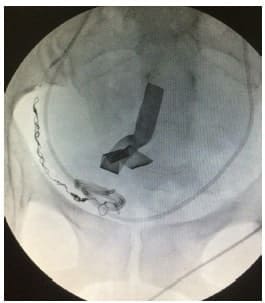

En primera instancia se realizó embolización con micropartículas (Contour, Boston Scientific, Massachusetts) y microesferas (Embosphere, Merrit Medical Systems Inc.) de 500 a 700 micras, con el objetivo de ir a los vasos más distales y posteriormente se complementaba con microcoils de platino Interlock, de 4 a 6 mm de diámetro por 40 cm de longitud (Boston Scientific, Massachusetts).

Se efectúo compresión manual después del retiro del introductor y vendaje, con reposo en cama por 12 horas (figura 2).

Figura 2. Elementos de embolización con micropartículas y microcoils

Clásicamente, el principal material de embolización utilizado ha sido el Gelfoam (gelatina de piel porcina purificada), pero ocurre reabsorción del material en 4 a 6 semanas, por lo que el uso de agentes más efectivos como las micropartículas y microesferas de polivinilo alcohol (500 a 900 micras), asociada a coils de platino o líquidos embolizantes (como el onyx o glue), permiten una oclusión permanente y segura del vaso elegido 24 (figura 5).

Figura 5. Embolización con microcoils